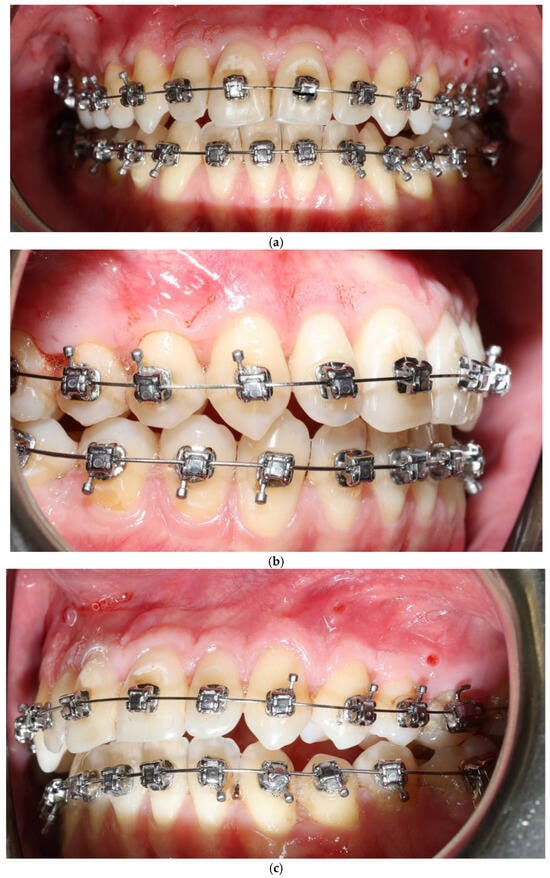

A 27-year-old female patient presented with a thin periodontal phenotype based on probe-transparency test, mild crowding in both arches, and narrow alveolar anatomy confirmed clinically and radiographically—Figure 1a–c. Thin phenotypes are known to present a significantly increased risk of buccal bone loss during expansion, especially when the cortical plate is critically thin at baseline [1,24,25,26].

Figure 1.

Patient 1—before treatment (a–c).

A 22-year-old female patient presented with: anterior open bite, maxillary constriction, crowding and a thin periodontal phenotype—Figure 3a–c.

Figure 3.

Patient 2 before treatment (a–c).

The vestibular soft-tissue phenotype appeared thicker, with reduced translucency and a more convex gingival contour. Gingival margin stability was maintained throughout therapy, and no recession, bleeding, or inflammation was present (Figure 4a–c). Outcome assessment in this case report is primarily qualitative and based on standardized clinical photography and clinical phenotype indicators (defined by periodontal probe transparency through the gingival margin), without quantitative soft-tissue thickness measurements.

Figure 4.

Patient 1 after treatment (a–c).

No adverse periodontal events were observed (Figure 5a–c). All changes in soft-tissue phenotype in the BPS arch occurred without any surgical augmentation.

Figure 5.

Patient 2 after expansion and BPS removal from the upper arch under treatment (a–c).